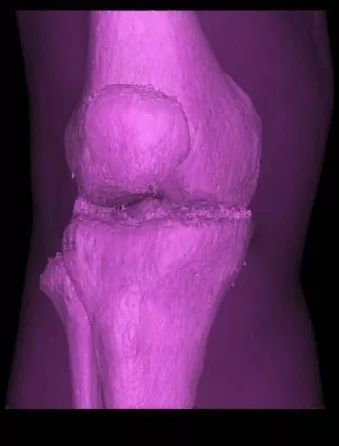

三维重建图

根据这些完整的实验数据,陈忆九作出判断:王秀芝腓骨小头骨折由撞击直接形成。

“陈老师认为,一方面摔倒致伤位置不符,作用力的大小也不符合摔伤形态;另一方面影像显示胫骨呈现倒T形骨折,符合撞击致伤的形态。”李正东说。